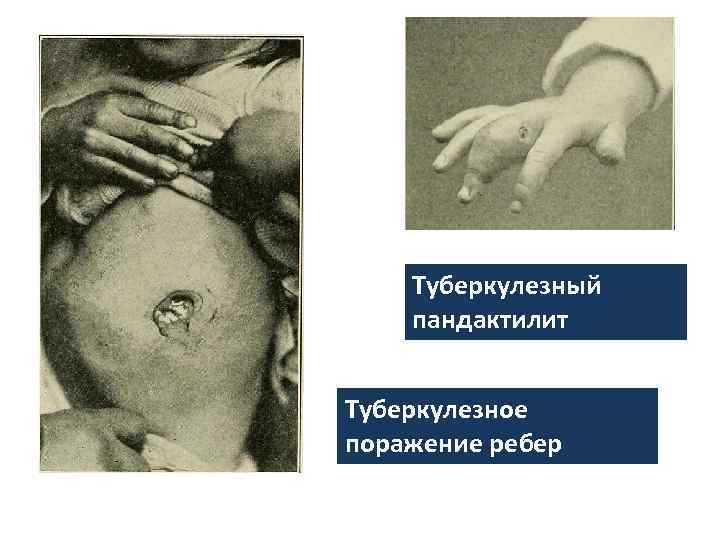

Туберкулезный пандактилит Туберкулезное поражение ребер

Туберкулезный пандактилит Туберкулезное поражение ребер